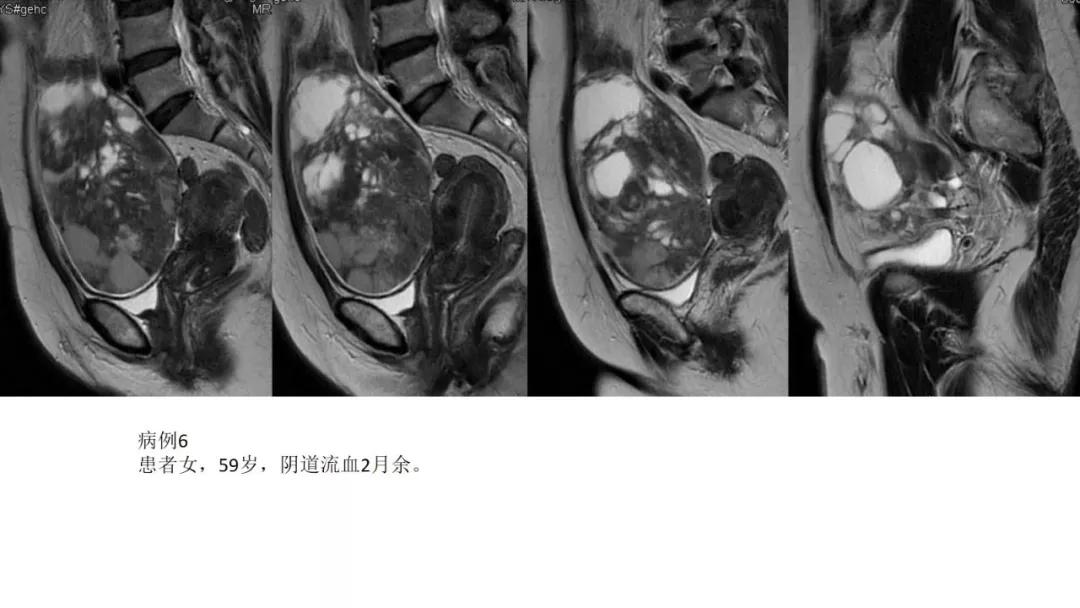

- 阴道不规则出血、闭经、量大:性索间质性肿瘤、子宫内膜样癌、透明细胞肿瘤

高雌激素症状:颗粒细胞瘤、卵泡膜细胞瘤(绝经期后出血及阴道不规则出血、性早熟、子宫内膜增生、乳房胀痛)